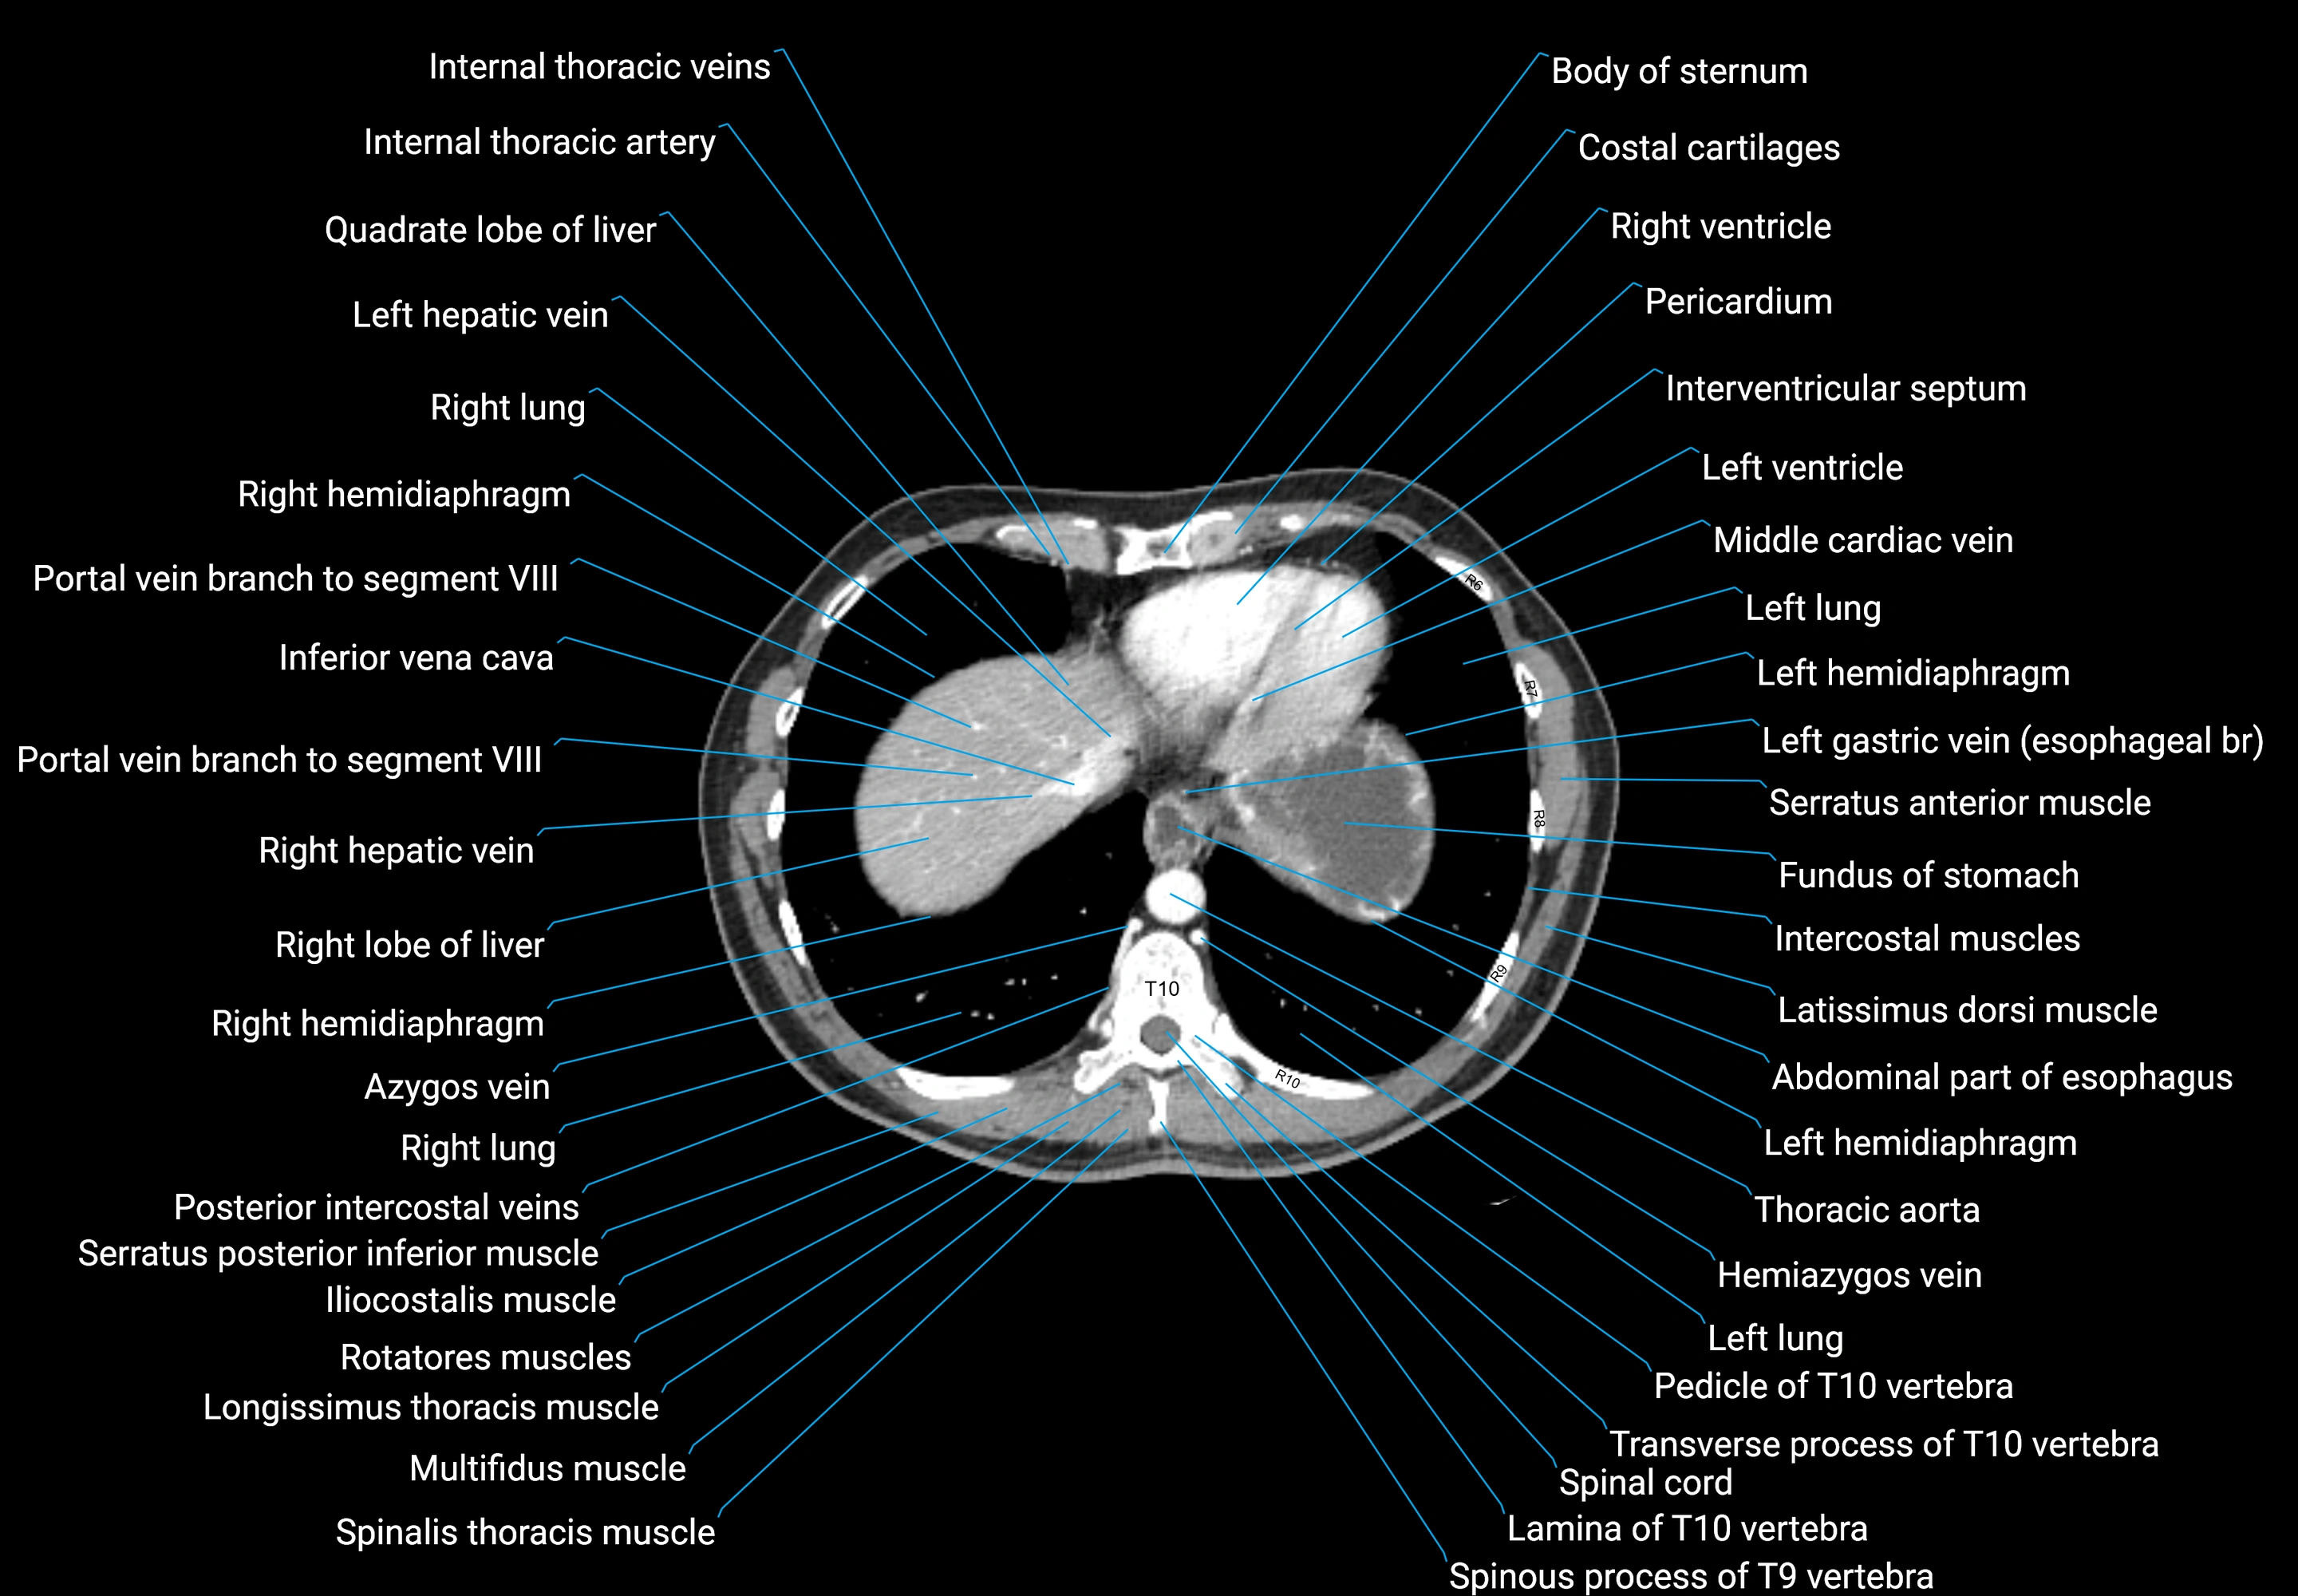

CT images